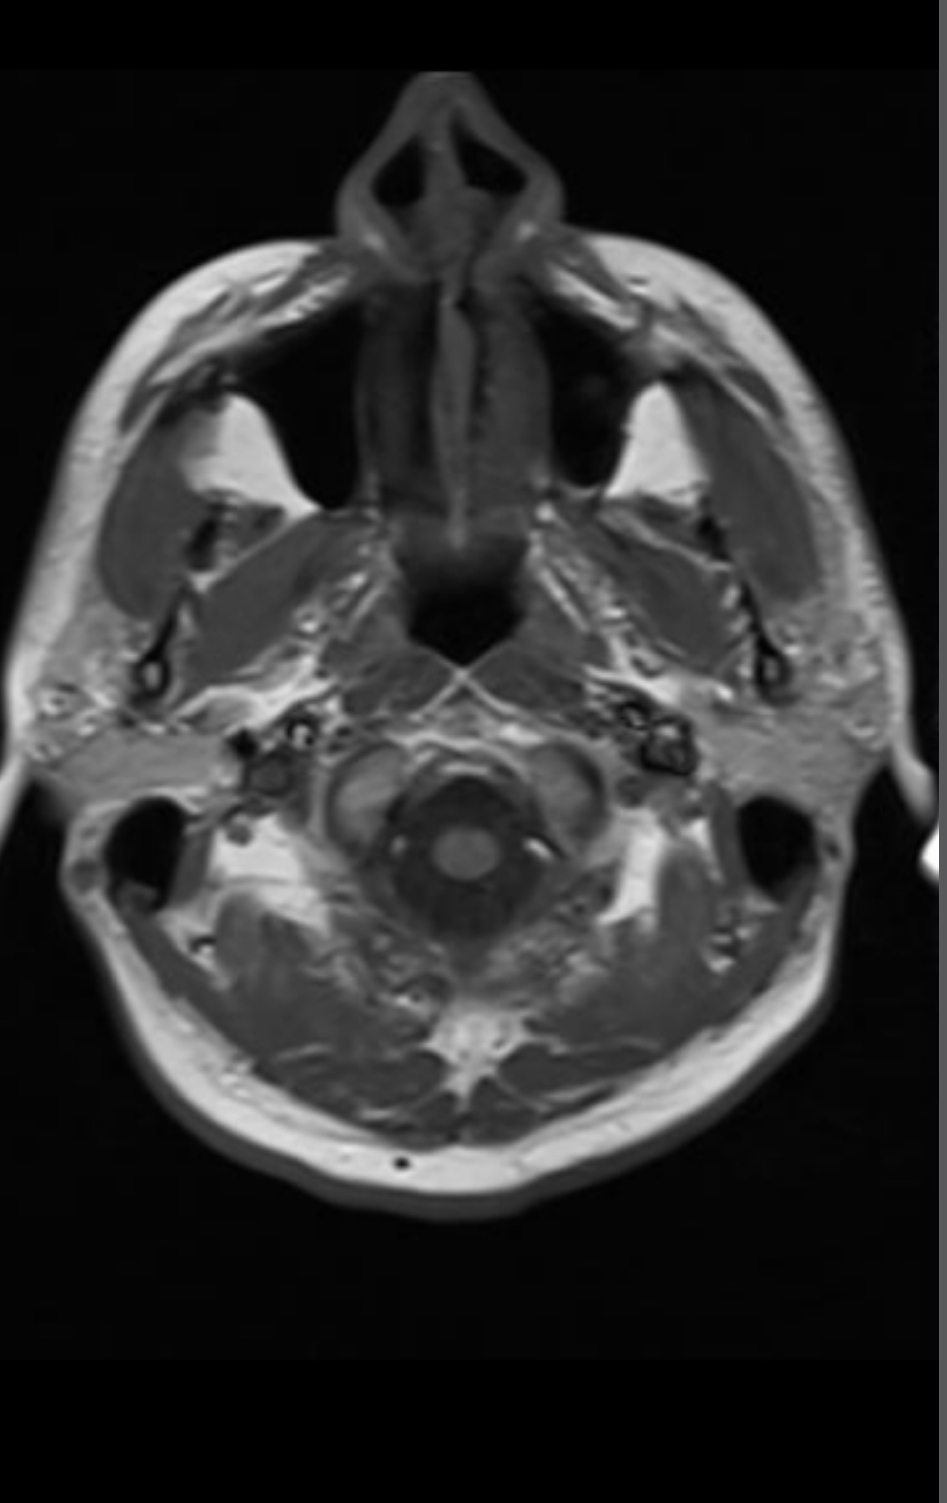

Arkadaşlar aranızda beyin emarı çektiren var mı yada bu konulardan anlayan ? Az önce emardan çıktım, emara sokan teknisyen pantolu ve kemerimi çıkartmadan emara soktu beni. Eee hani metal eşya ile girmek sakıncalı ve yasak degilmiydi? Şuan beynim şişmiş gibi acayip ağırlık var beynimde . Umarım bu emar sağlığa zararlı değildir. Radyasyon olmadığı için zararsız diyorlar ,umarım doğrudur. Hadi bunu geçtim ama o kemer umarım emar sonuçlarını etkilemez. < Bu mesaj bu kişi tarafından değiştirildi berlin007 -- 28 Eylül 2022; 23:49:8 > < Bu ileti mobil sürüm kullanılarak atıldı > |